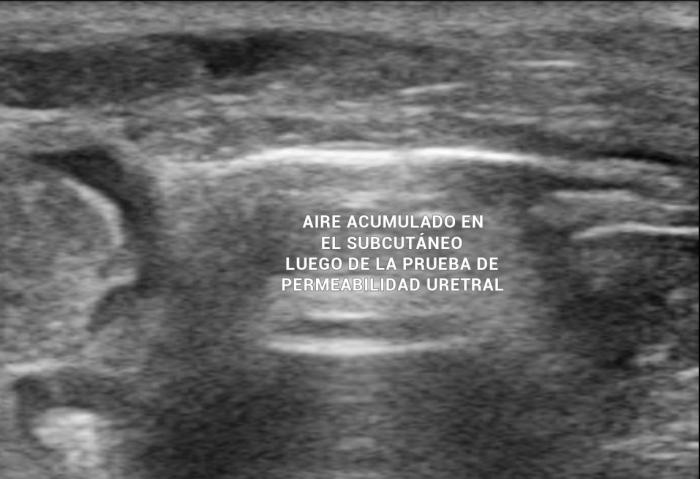

Mediante el estudio ultrasonográfico se detectó la presencia de líquido acumulado en la cavidad pélvica, en la zona peri-uretral, con esteatitis asociada (Figura 5). Debido a estos hallazgos se sospechó una ruptura traumática de la uretra, por lo cual se sometió a la paciente a una prueba de contraste uretral positivo, la cual evidenció la perforación uretral (Figura 6).

Luego de un corto tiempo, el aire introducido se acumula en el subcutáneo (Figura 7) (Vídeo 2).